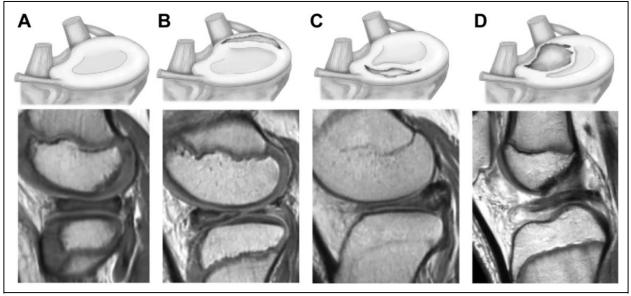

图片来源:doi: 10.1177/23094990211022043.

外侧盘状半月板损伤的Ahn分类方法:(A)半月板无明显移位,(B)半月板后角纵向撕裂对应的中心前移位,(C) 半月板前角的纵向撕裂后中心移位,(D)中心移位对应于外侧角丢失